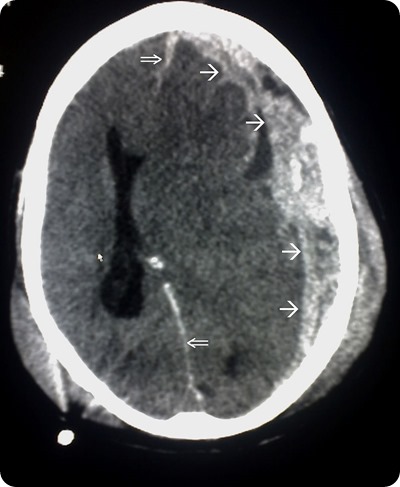

Neuroimaging is a key technique in terms of diagnosing SBS. Intracranial pathologies such as cerebral edema and subdural and subarachnoid hemorrhage may be identified with the help of CT scans. These scans are usually the tool of choice in emergency situations.

CT scan flowing head trauma, the single arrows mark the spread of the subdural haematoma and the double arrows mark the midline shift. Source: commons.wikimedia.org